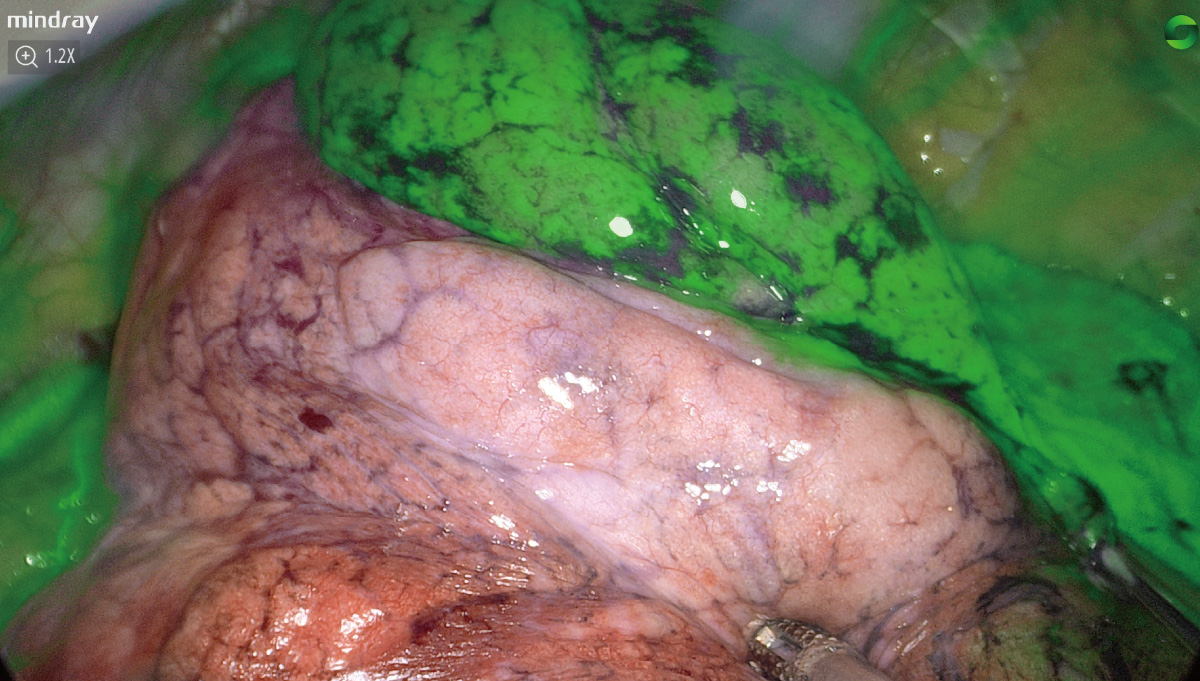

PercepciĂłn sensiblenavegaciĂłn precisa

El avance en la tecnologĂa de fluorescencia aumenta significativamente la sensibilidad de detecciĂłn y la estabilidad de la imagen de fluorescencia, lo que hace mĂĄs precisala navegaciĂłn.

El avance en la tecnologĂa de fluorescencia aumenta significativamente la sensibilidad de detecciĂłn y la estabilidad de la imagen de fluorescencia, lo que hace mĂĄs precisala navegaciĂłn.

Sensibilidad ultra alta de la fluorescencia

La doble optimizaciĂłn de excitaciĂłn e imagen reduce la sensibilidad de la captura de se?al de fluorescencia al nivel de los nanomoles, lo que favorece la detecciĂłn clĂnica de peque?as lesiones metastĂĄsicas con dosis bajas y ofrece una mayor capacidad de penetraciĂłn con la misma dosis.

Algoritmo de estabilizaciĂłn de la fluorescencia

VisualizaciĂłn precisa del ĂĄrea de imagen con verde de indocianina, eliminaciĂłn eficaz de la atenuaciĂłn de se?al causada por la distancia y la desviaciĂłn del ĂĄngulo, gran estabilidad de la fluorescencia y adecuada divisiĂłn de los mĂĄrgenes.

FusiĂłn de fluorescencias a nivel de pĂxel

El estricto control del proceso de montaje ayuda a obtener la fusiĂłn y alineaciĂłn pĂxel a pĂxel de la imagen de luz blanca y fluorescencias. La imagen de fluorescencias con detalles de textura de luz blanca tambiĂ©n puede ayudar en todo el proceso quirĂșrgico guiado por fluorescencia

Casos clĂnicos

EvaluaciĂłn de perfusiĂłn sanguĂnea en anastomosis colorrectal

La resecciĂłn hepĂĄtica laparoscĂłpica (RHL)

Mapeo de ganglio linfĂĄtico centinela en cĂĄncer de endometrio

ResecciĂłn pulmonar anatĂłmica sublobar